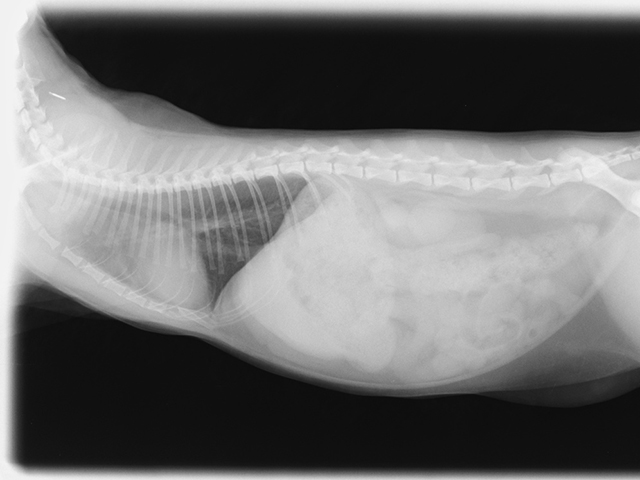

投薬開始2か月後(2022.2.23)

投薬開始後数日で胸水解消、1カ月後には血液検査も正常値に。